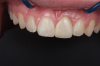

Fig 3. Implants were placed in a 20-year-old female patient in the Nos. 7 and 11 sites with a pontic replacing No. 10.

Fig 4. A 15-year postoperative photograph of the patient in Fig 3 illustrates the significant infraocclusion of the implants compared to the natural teeth. Also, note the blue tissue discoloration over implants Nos. 7 and 11.

A third risk of using an implant to replace a missing lateral incisor is the continued vertical growth of the alveolar bone and eruption of the teeth adjacent to the implant.9,10 Traditionally, it has been taught that an implant can be safely placed when alveolar bone growth is confirmed complete with serial radiographs. However, numerous studies call that rule into question.11-16 Bernard et al evaluated vertical changes in teeth adjacent to implants in a young group of patients (15.5 to 21 years) and in a mature group (40 to 55 years), over a mean time of 4.2 years.17 In the young group, infraocclusion of the implant crowns ranged from 0.1 mm to 1.65 mm, while in the mature group the infraocclusion of the implant crowns ranged from 0.12 mm to 1.86 mm. An example of infraocclusion that occurred in a young implant patient over time is depicted in Figure 3 and Figure 4. Based on classic literature as cited here, it seems prudent to delay the placement of implants in high-risk areas, such as the maxillary lateral incisor region, for as long as possible or perhaps avoid it altogether.